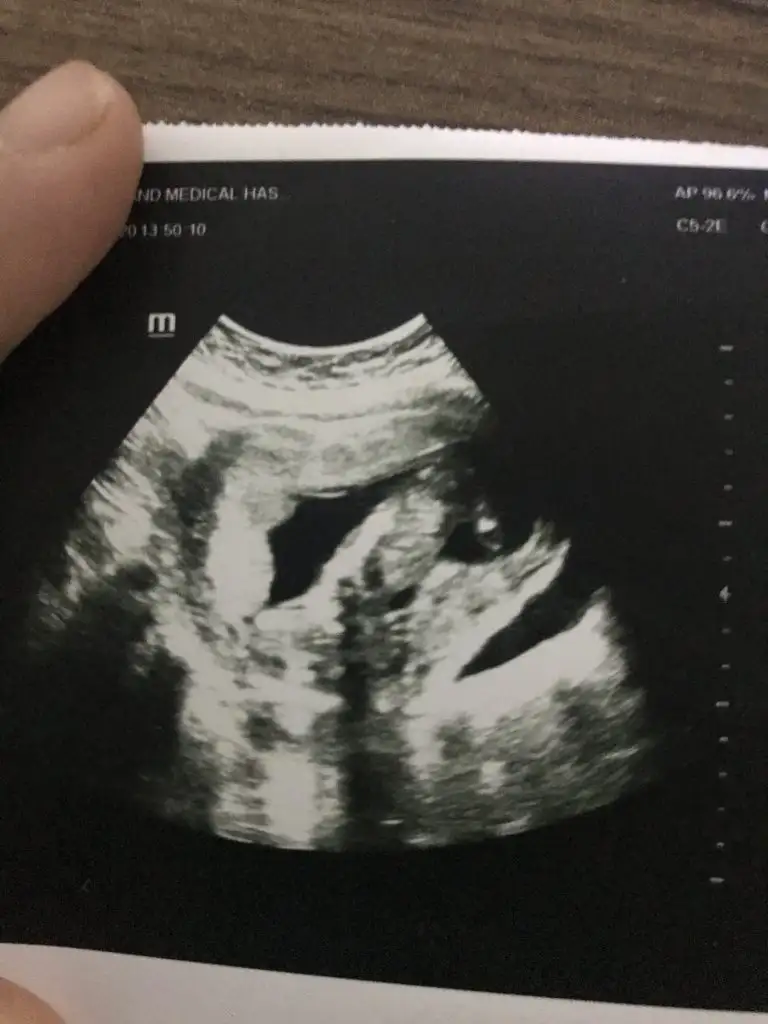

dün gittik 14 hafta usg verdi ama belli olmuyor

Buda kız gibi boş görünüyor bacak arasıdün gittik 14 hafta usg verdi ama belli olmuyor Eki Görüntüle 2575104

birdahaki kontrol sonucunu size bildireceğimKız bence 9+6 hafta ya göre![]()